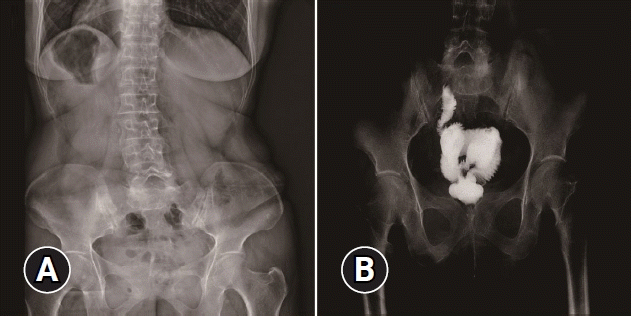

After resection, plain abdominal radiography revealed no pneumoperitoneum, indicating the absence of intestinal perforation (Fig. 3A). A barium enema demonstrated a wide, patent anastomosis, confirming the success of the endoscopic resection (Fig. 3B). Three days after the procedure, an ileostomy reversal was performed, and the patient was discharged after a 7-day hospital stay. The patient remained healthy throughout the 1.5-year follow-up period.